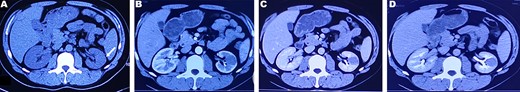

A 37-year-old male underwent a computed tomography scan (CT), which revealed a 2.5 × 1.9 cm slightly lower density ingrown mass in the lower pole of left kidney for 1 month. The patient was asymptomatic and had a history of kidney stones. The shape of the mass was regular, with unclear boundaries. Enhanced CT showed that the enhancement of the mass was lower than that of the surrounding renal parenchyma (Fig. 1). On magnetic resonance imaging (MRI), a circular abnormal signal was detected in the cortical medullary area of left kidney, with an equal signal on T1WI and a slightly low signal on T2WI (Fig. 2A and B). The enhanced MRI scan showed no obvious enhancement in the cortical and medullary phases and a slightly dotted high signal in the excretion phase (Fig. 2C–F). The mass was a space-occupying ingrown lesion with insufficient blood supply. Patients underwent laparoscopic partial nephrectomy and received no postoperative therapy. After the tumor was incised, a 2.3 × 2 cm soft mass that was grayish-white and slightly grayish-yellow was found with clear boundary. Histology (hematoxylin and eosin staining) results showed that the tumor was composed of elongated tubules arranged in parallel. The tubules lined with cuboid and spindle cells set in a small amount of myxoid matrix (Fig. 3A). Most of the tumor cells were round, a few were spindle and elliptical, with eosinophilic nucleoli. Mitotic figures were rare and the atypia is not obvious. Obvious foamy macrophage aggregates could be seen in some areas (Fig. 3B). Immunohistochemical results were as follows: CK7(+), P504S (+), PAX-8(+), CD10(−) (Fig. 3C–F). The Ki67 stain showed proliferation rates up to 5%. The pathological result demonstrated left renal mucin-poor MTSCC. We performed next-generation sequencing (NGS) for case, and the result showed that the tumor mutational burden was 2.74 mutation/Mb. RET gene mutation was considered as a mutation of uncertain significance. The detection of multiple genetic polymorphism sites of tumors shows that it may be slightly sensitive to some chemotherapeutics like gemcitabine. PD-1/PD-L1 immunotherapy may not benefit the patient. The patient was followed up for 8 months after surgery. No evidence of metastasis or recurrence was found.

CT plain scan and enhanced scan of mucus-poor MTSCC. (A) CT scan showed a low-density mass in the lower pole of the left kidney (arrow), unclear boundary, swelling growth in kidney; (B) enhanced CT scan of corticomedullary phase shows tumor mild homogeneous enhancement, (C) nephrography phase, (D) renal excretion phase.

MTSCC was classified into ‘classic’ and ‘mucin-poor’ based on the proportion of interstitial mucin in histology [4]. Few studies individually described the imaging characteristics of mucin-poor MTSCC. In all phases of enhanced CT, the mean attenuation of MTSCC tumor was not only less than the normal renal cortex and medulla, but also less than collecting duct carcinoma [5–7]. The tumors presented homogeneous pattern enhancement and were usually small (≤5 cm) [6]. In MRI scans, the T1WI signal was isointense to normal renal parenchyma. T2WI signal was usually diverse, including hypo-, iso- and hyperintensity [5]. In our study, tumors presented low-signal intensity on T2w images. This may be related to no mucinous or myxoid stroma. It may be a significant feature to distinguish mucin-poor MTSCC and classic MTSCC on imaging diagnosis.